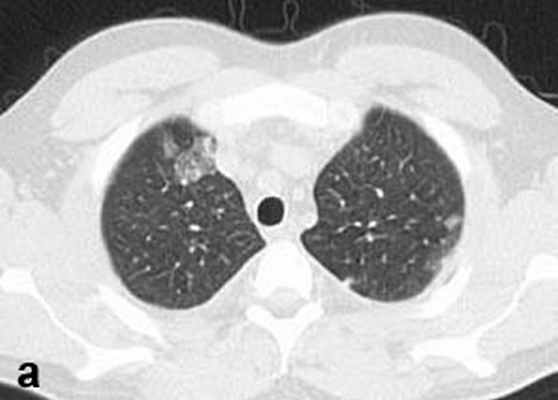

Больной С., 33 г., по профессии электромонтажник, поступил в НМХЦ им. Н.И. Пирогова 5 февраля 2007 г. с жалобами на одышку при незначительной физической нагрузке, кашель с трудноотделяемой мокротой слизистого характера, общую слабость, похудание на 10 кг, субфебрильную температуру тела. С 2000 г. у пациента диагностировали хронический ринит, синусит, полипоз носа. Для купирования затрудненного носового дыхания последние 3 года применял кортикостероидный назальный спрей. В связи с возникновением приступов удушья 2006 г. в НИИ аллергологии и иммунологии диагностирована бронхиальная астма среднетяжелого течения. Назначена терапия симбикортом с положительным эффектом. Ухудшение состояния с декабря 2006, когда появились субфебрильная температура тела, приступы затрудненного дыхания, одышка при физической нагрузке, снижение аппетита. При КТ органов грудной клетки, выполненной амбулаторно 25.01.07г.: лимфаденопатия средостения (лимфоузлы до 2-2,5 см) с образованием конгломерата размером 38 х 40 х 50 мм (рис. 1), снижение прозрачности легочной ткани по типу «матового стекла» (рис. 2а), диффузное уплотнение интерстициальной ткани (рис. 2б), двусторонний гидроторакс. Заподозрена опухоль переднего средостения в связи, с чем пациент госпитализирован для морфологической верификации диагноза.

| Рис. 2. КТ грудной клетки: а - снижение прозрачности по типу “матового стекла“, б - диффузное уплотнение интерстициальной ткани. | |